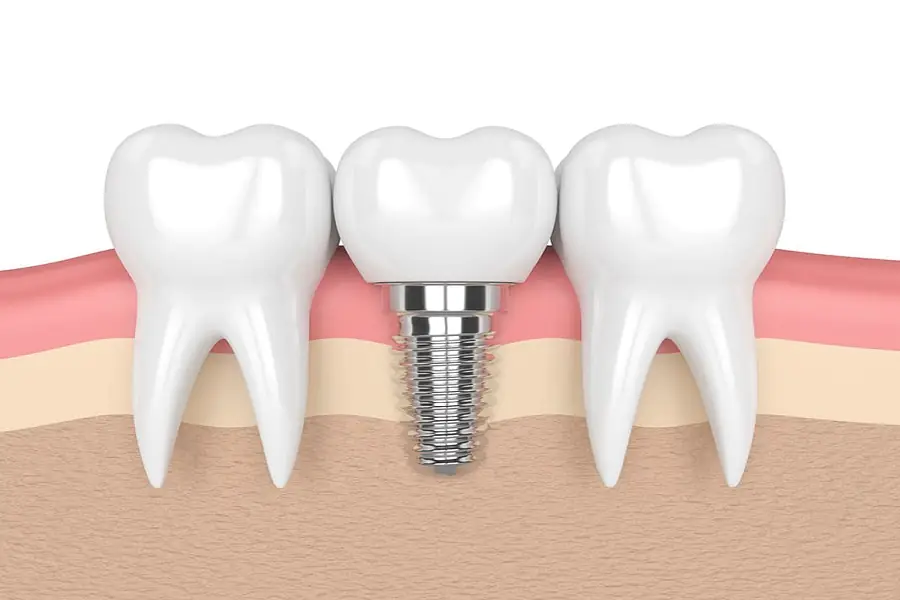

Although dental implants are the best way to repair missing teeth, for patients with missing teeth, they do not know whether they can do dental implants because of the different age stages of tooth loss. If there is no requirement, is there any age requirement for dental implants???

Young edentulous patients have strong metabolism and high bone density. After tooth extraction, the alveolar bone heals quickly and the healing quality is high, and the success rate of dental implants is relatively high. The elderly have relatively loose bone and obvious alveolar bone resorption, but this does not mean that the elderly cannot have dental implants.??

In fact, a considerable number of elderly patients with missing teeth are suitable for dental implant restoration. For patients with poor alveolar bone conditions, dentists can implant bone before implant surgery to increase the height and width of the alveolar bone, and the postoperative alveolar bone can fully meet the requirements of dental implants. The general physical condition or the elderly with a certain disease but well controlled, as long as they can withstand tooth extraction, dental implant surgery can be performed to complete the implant restoration.??

As early as the early 1990s, there were successful cases of 80-year-old patients undergoing dental implant restoration. The appearance of dental implants has effectively changed the situation of strong foreign body sensation and easy loosening of traditional dentures. It is beautiful, firm, comfortable, with little foreign body sensation and high chewing efficiency, which will undoubtedly greatly improve the quality of life of elderly patients with missing teeth. more and more favored by elderly patients.